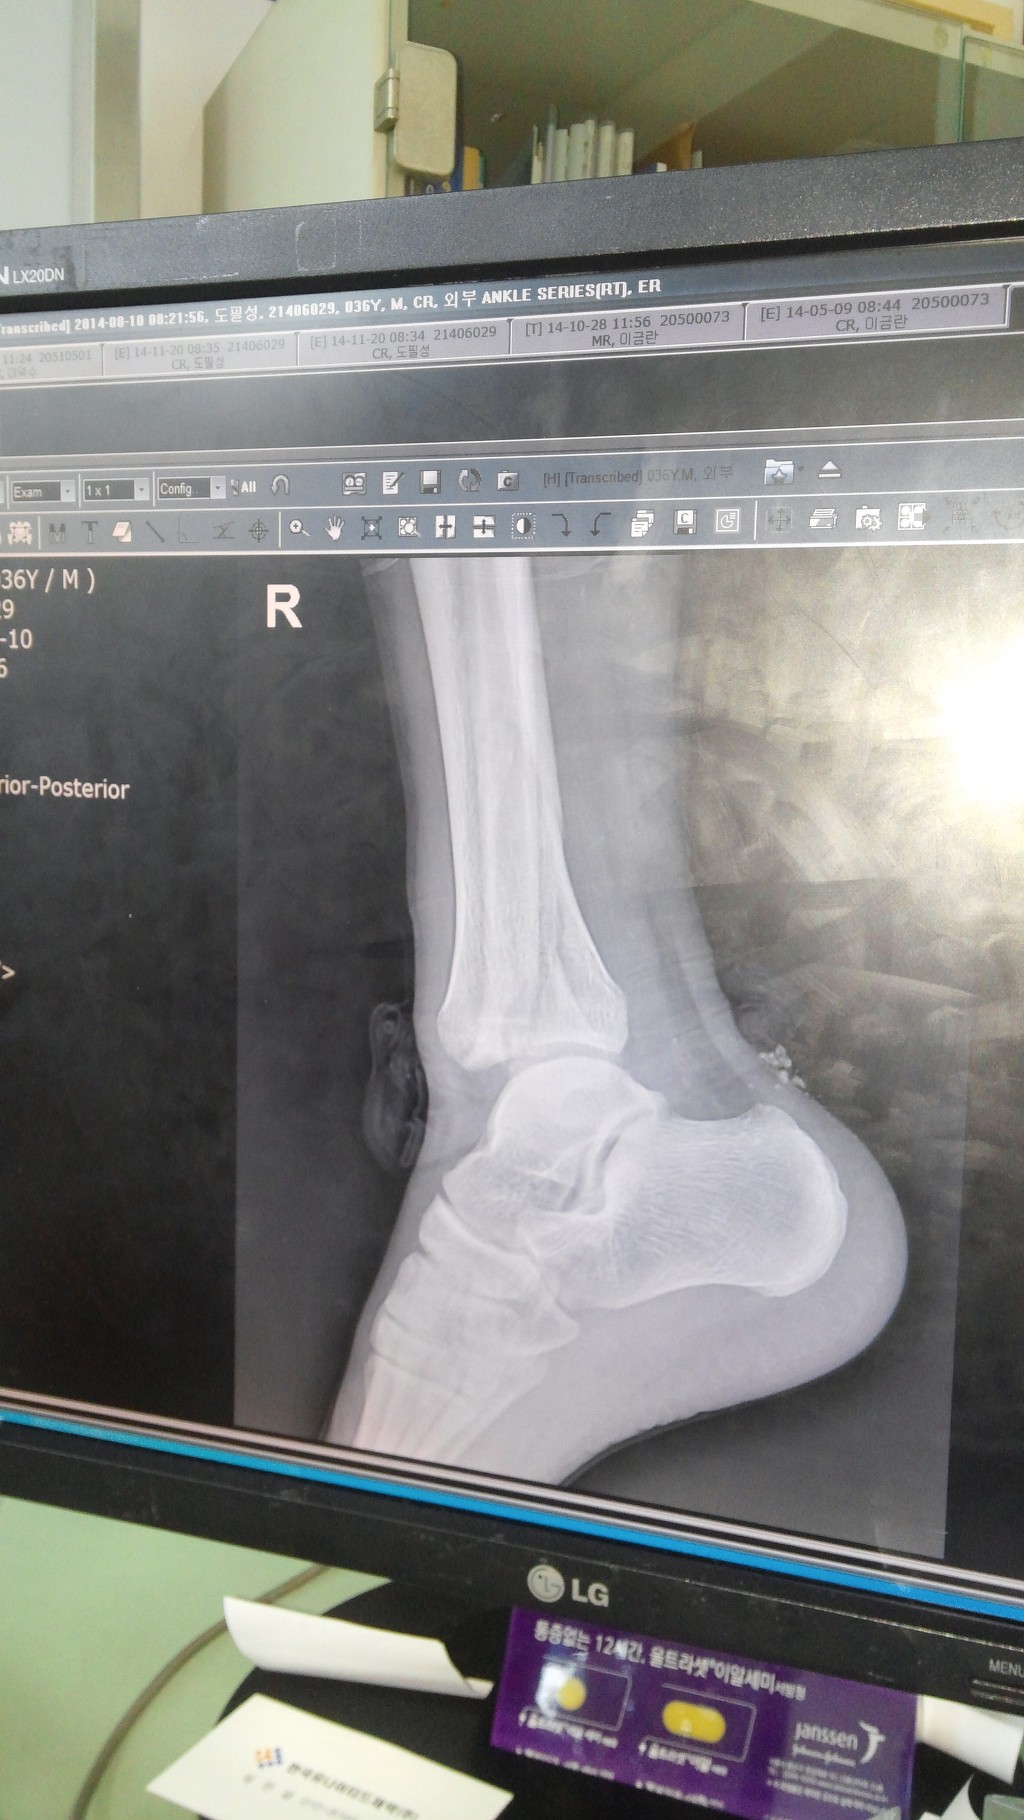

우측 족관절 원위 경골 관절내 골절, 외측과 골절, 후과 골절 수술 및 재활 과정 적습니다.15주차입니다.

8월 10일 오전 07시 평소 즐겨하던 사회인 야구를 하다가 무리한 슬라이딩으로 인한 우측 발목 위 골절이 일어났습니다. 제가 달려가는 주자였고 상대팀 포수와 그대로 충돌하였습니다.

119와서 응급실 그대로 실려갔습니다.집이 먼 관계로 응급처치만 받고 몇 시간후 와이프가 와서 집 근처 준종합병원으로 입원하였습니다.일요일이라 아무 조치도 없이 하루 보냈습니다. 물론 진통제 맞고 하였지요. 낮에는 그나마 참을만 했습니다만 밤에 자려는데 통증 정말 미치겠더군요.밤새 깨다 잠들다를 반복. 고통의 시간이였습니다. 그러다 다음날 월요일 아침. 주치의가 오셨고 붓기 때문에 바로 수술은 안되고 수요일나 금요일 하자고 하더군요. 붓기 상태보고요.

다행히 붓기가 빠져서 13일 수술하였습니다. 4시간 수술하였고요. 하반신 마취하였습니다. 무통 달아놔서 그런지 큰 통증은 없었습니다.수술후 마취가 안 풀려 오줌은 마려운데 나오지가 않으니 통증이 장난 아니더군요. 휴~